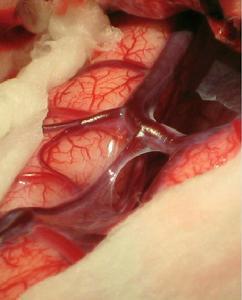

核磁共振成像儀 造影時可發現瘺的供血動脈及引流靜脈均有不同程度的迂曲擴張,當靜脈竇壓力過高,皮層靜脈回流不 暢時,特別是直接由皮層靜脈引流的硬腦膜動靜脈瘺可見有瀰漫性皮層靜脈擴張、迂曲呈蚯蚓狀或瘤樣擴張,引流靜脈或靜脈竇常在動脈期即顯影,但靜脈竇循環時間較正常的循環時間長。

(2)引流靜脈呈靜脈瘤樣擴張,有破裂可能。開顱翻骨瓣時要特別小心,因為硬腦膜上充滿了動脈化的靜脈血管。如瘺口位於竇壁,血管內栓塞欠佳者,可開顱切開竇壁,直接行竇內銅絲填塞,效果肯定。